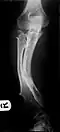

Múltiples osteocondromas que causan deformidad del antebrazo (acortamiento del radio con arqueamiento secundario del cúbito ). -